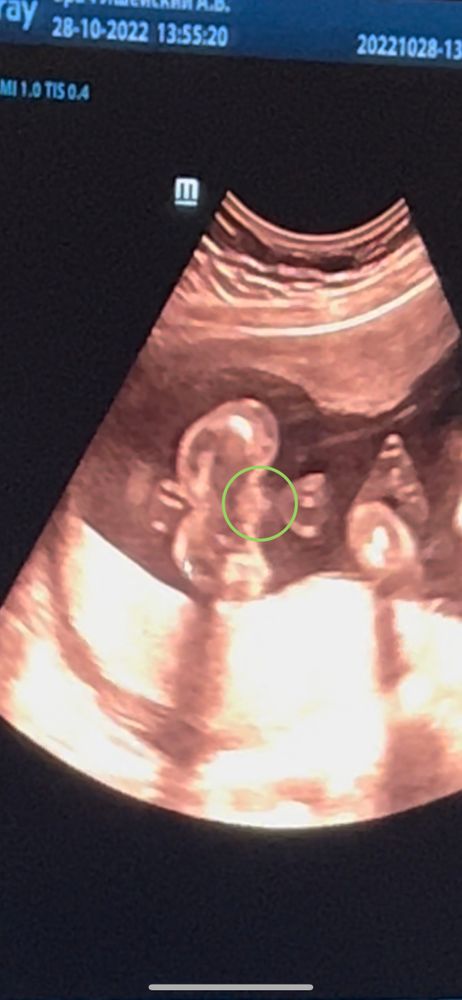

Вопросы про УЗИ, обследования и анализы: что, где, как, когда?Привет девочки , назрел вопрос )) Начну с предыстории: Первый скрининг в 13 недель , на узи сказали , что плод похож на пацана . Дождалась 17 недель , делала узи в платной клинике , сказали : «похоже на девочку» И в этот момент я все снимала , так обрадовалась что девочка и имя придумала ещё раньше , а в душе знаю что пацан 😂 Пересматриваю кадры с узи , и уловила вот такой интересный момент *фото ниже 👇

Как думаете , кто же это может быть ?😅

Дополняю : нам уже 1,8 мес . мой мальчик Дима уже совсем большой ) В итоге в 25 недель в государственной поликлинике тыкнули пальцем в экран , и сказали : « да какая девочка , у вас тут МУЖИК» 😸

Аналогично)) сказали парень на первом скрининге, сегодня на втором сказали девочка. А я вот это на видео увидела 🤷♀️

Скорее всего девочка и есть ,раз врач предположила,а по фото как то не понятно, может пуповина торчит.